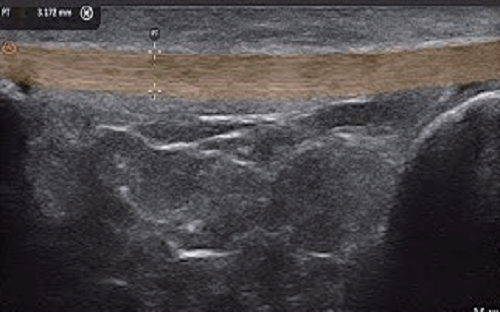

PAU2C aesthetic skin ultrasound device is portable and easy to use for aesthetic medicine. Handheld design allows aesthetic physicians to perform ultrasound whenever patients are in need. Aesthetic medicine ultrasound device works for medical beauty, clinic, hospitals, beauty salon. Our medical beauty ultrasound device that connects with WIFI without restrictions of wiring. Support windows, android, and IOS. Supported ultrasound exam presets for cosmetic medical services include fat factor, HA, PCL, CaHA, PLLA and PDLLA.

PAU2C is a game-changing ultrasound device for aesthetic and medical professionals, combining intuitive usability with advanced features to meet modern clinical and beauty workflow demands. Whether used to evaluate fat distribution, track filler efficacy, or assess tissue response, PAU2C delivers the precision, speed, and dependability professionals need for exceptional patient outcomes.

PAU2C redefines portability and user-friendliness in dermatological ultrasound. Its compact handheld design breaks bulky equipment constraints, enabling aesthetic physicians to provide on-demand skin ultrasound assessments during consultations, follow-ups, or on-site services. This flexibility makes it indispensable across settings: medical beauty clinics, private practices, hospitals, and high-end beauty salons—adapting seamlessly without compromising accuracy or performance.